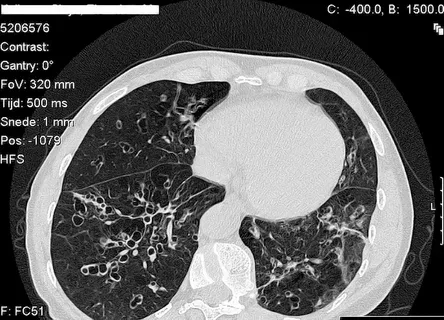

Alpha-1 symptoms shown in clinical respiratory assessment

• The most common alpha-1 symptoms involve the lungs, including shortness of breath, wheezing, and chronic cough, often diagnosed as genetic COPD.